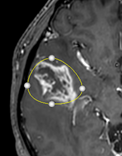

Polygon (spline) ROI

The

polygon ROI is initially displayed as a circle with four anchor

points that can be moved to change the shape of the ROI. Additional anchor

points can be added by <ctrl>+ right button click. The whole ROI can be

moved by left-clicking anywhere on the ROI line.